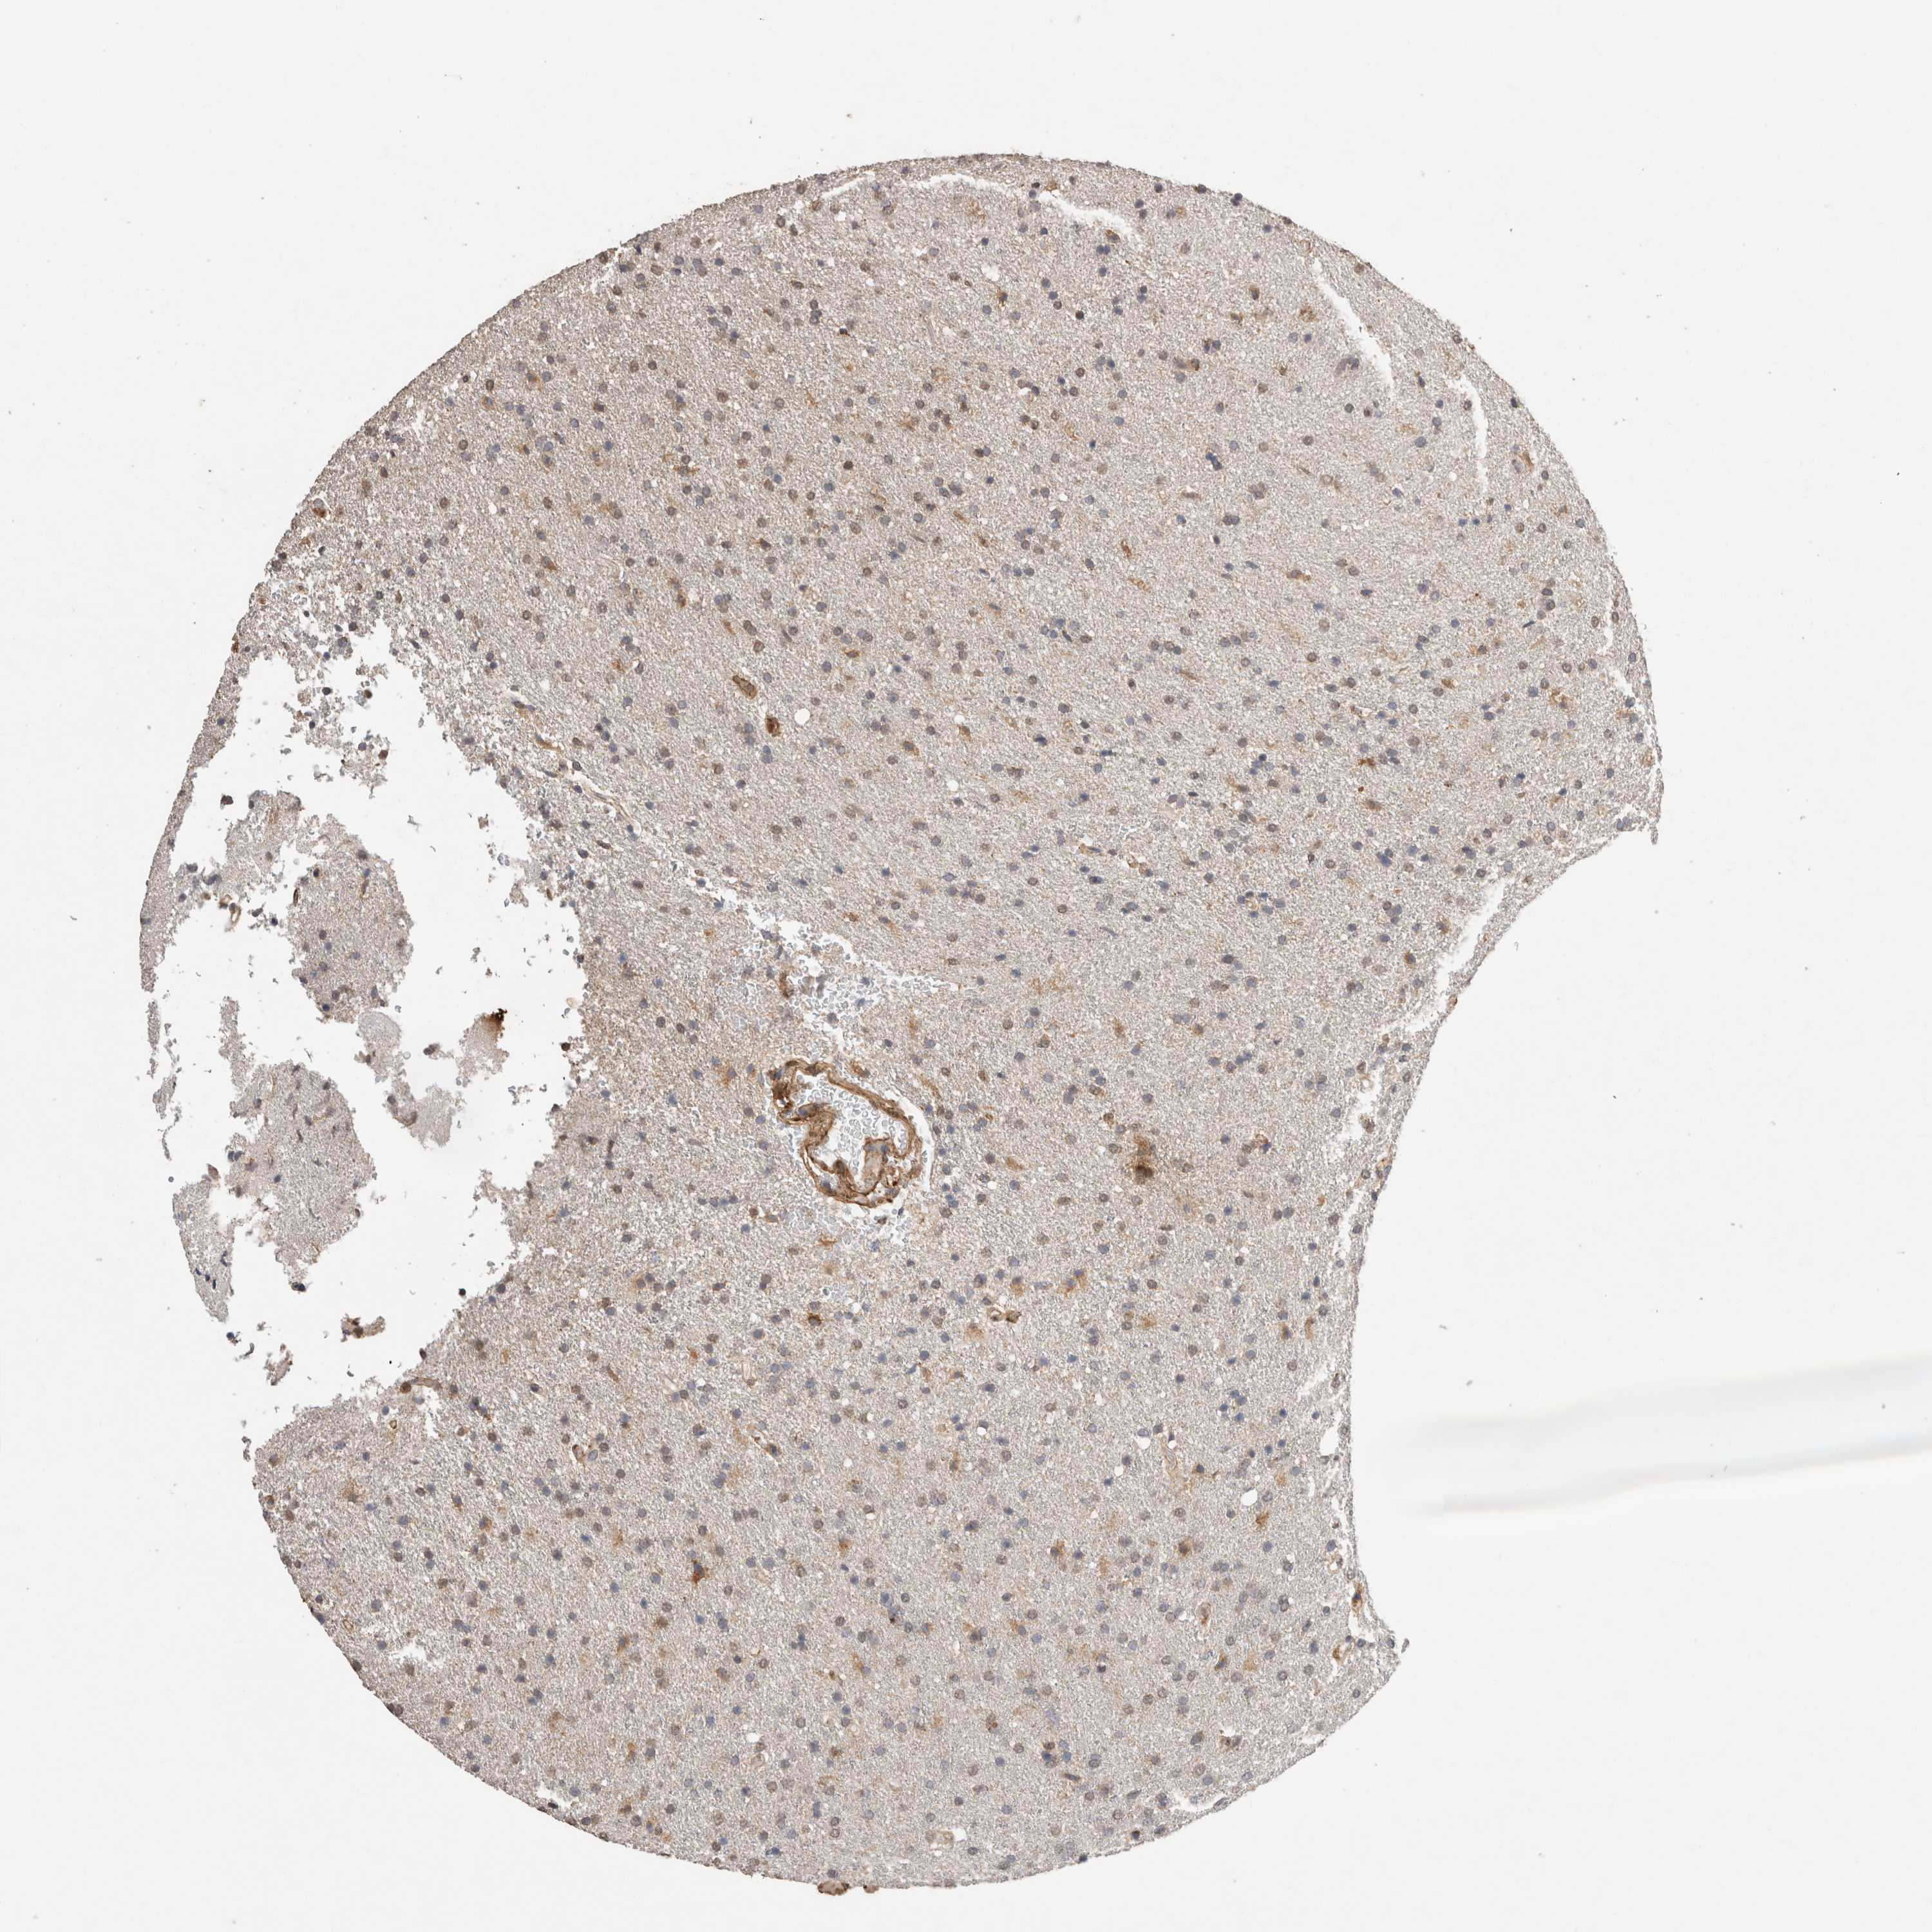

GLIOMA - Protein expressioni

A mouse-over function shows sample information and annotation data. Click on an image to view it in a full screen mode. Samples can be filtered based on level of antibody staining by selecting one or several of the following categories: high, medium, low and not detected. The assay and annotation is described here.

Note that samples used for immunohistochemistry by the Human Protein Atlas do not correspond to samples in the TCGA dataset.

Antibody stainingi

Antibody staining in the annotated cell types in the current human tissue is reported as not detected, low, medium, or high, based on conventional immunohistochemistry profiling in selected tissues. This score is based on the combination of the staining intensity and fraction of stained cells.

Each image is clickable and will lead to virtual microscopy that enables deeper exploration of all samples and also displays staining intensity scores, fraction scores and subcellular localization as well as patient and tissue information for each sample.

Antibody HPA038604

Antibody CAB025607

Staining

High

Medium

Low

Not detected

Intensity

Strong

Moderate

Weak

Negative

Quantity

>75%

75%-25%

<25%

None

Location

Nuclear

Cytoplasmic/membranous

Cytoplasmic/membranous,nuclear

Glioma, malignant, High grade

Glioma, malignant, Low grade